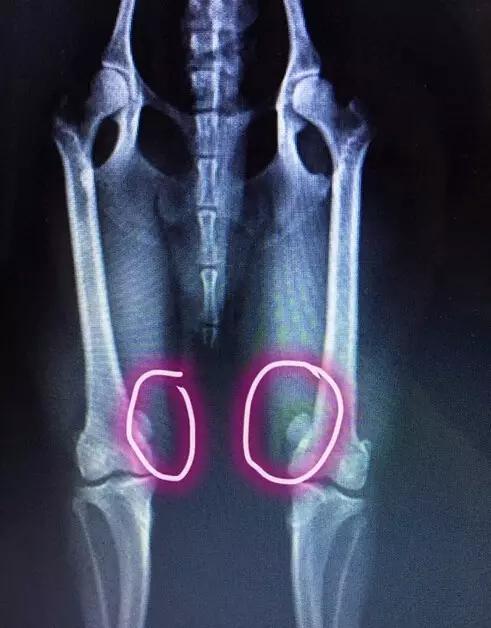

主人心急带奔奔去医院拍片检查,结果是髌骨脱臼。

简单来说~其实髌骨就是膝盖骨,在大腿的四头肌头下~通常髌骨在骨关节的凹槽中,但是如果狗狗经常做一些违反“狗体原理”的动作,髌骨会脱出这个凹槽。

而且不及时治疗,它会导致胫骨和骨骨骼变形,甚至会导致狗狗下半身瘫痪。